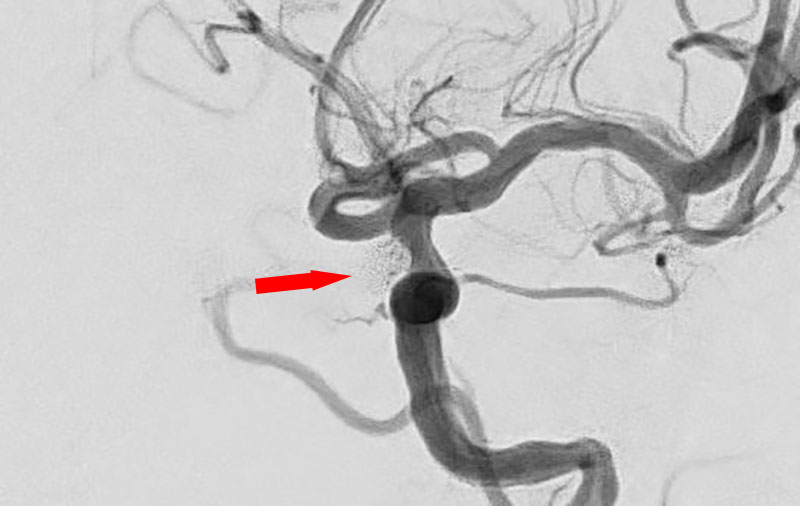

No.1627 手術前

No.1627 手術中

No.1627 手術後